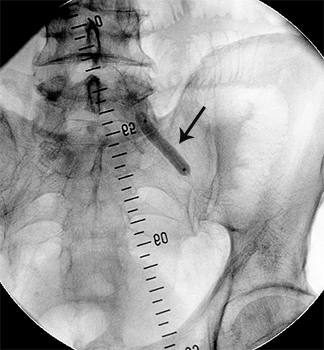

Приклади ангіограм до та після дилятації:

стеноз лівої клубової артерії    балон, роздутий в зоні стенозу    відновлення отвору клубової артерії

Значний стеноз лівої

наружної клубової артерії

Балон-катетер,

роздутий в зоні стенозу

Отвір артерії відновлено на 80%